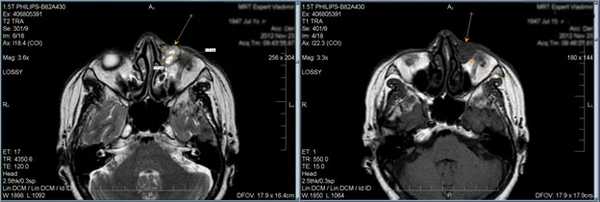

Тот же пациент, исследование в динамике через 4,5 года

Исследование в 2008 году Исследование в 2013 году

2. Синдром Толоза-Ханта (болезненная офтальмоплегия, синдром верхней глазничной щели)

Характеризуется вовлечением в процесс всех структур, проходящих через верхнюю глазничную щель (артерия, вена, отводящий нерв, блоковый нерв и глазодвигательный нерв, первая ветвь тройничного нерва), и прилегающего к ней кавернозного синуса. Субъективные проявления cиндрома Толоза-Ханта: болезненность в области орбиты, двоение в глазах, экзофтальм и хемоз.